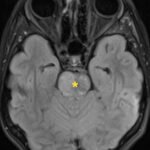

There is a growing body of literature and scientific discovery on pediatric autoimmune encephalitides. This is a heterogenous group of neuroinflammatory conditions leading to often perplexing acute and progressive neurologic and/or neuropsychiatric symptoms. This report demonstrates the evaluation and management of an adolescent with myelin-oligodendrocyte glycoprotein (MOG) antibody-associated fulminant acute disseminated encephalomyelitis (ADEM) in the context of current literature. The featured magnetic resonance imaging uniquely highlights progressive central nervous system lesions detected over the course of the first week of disease.